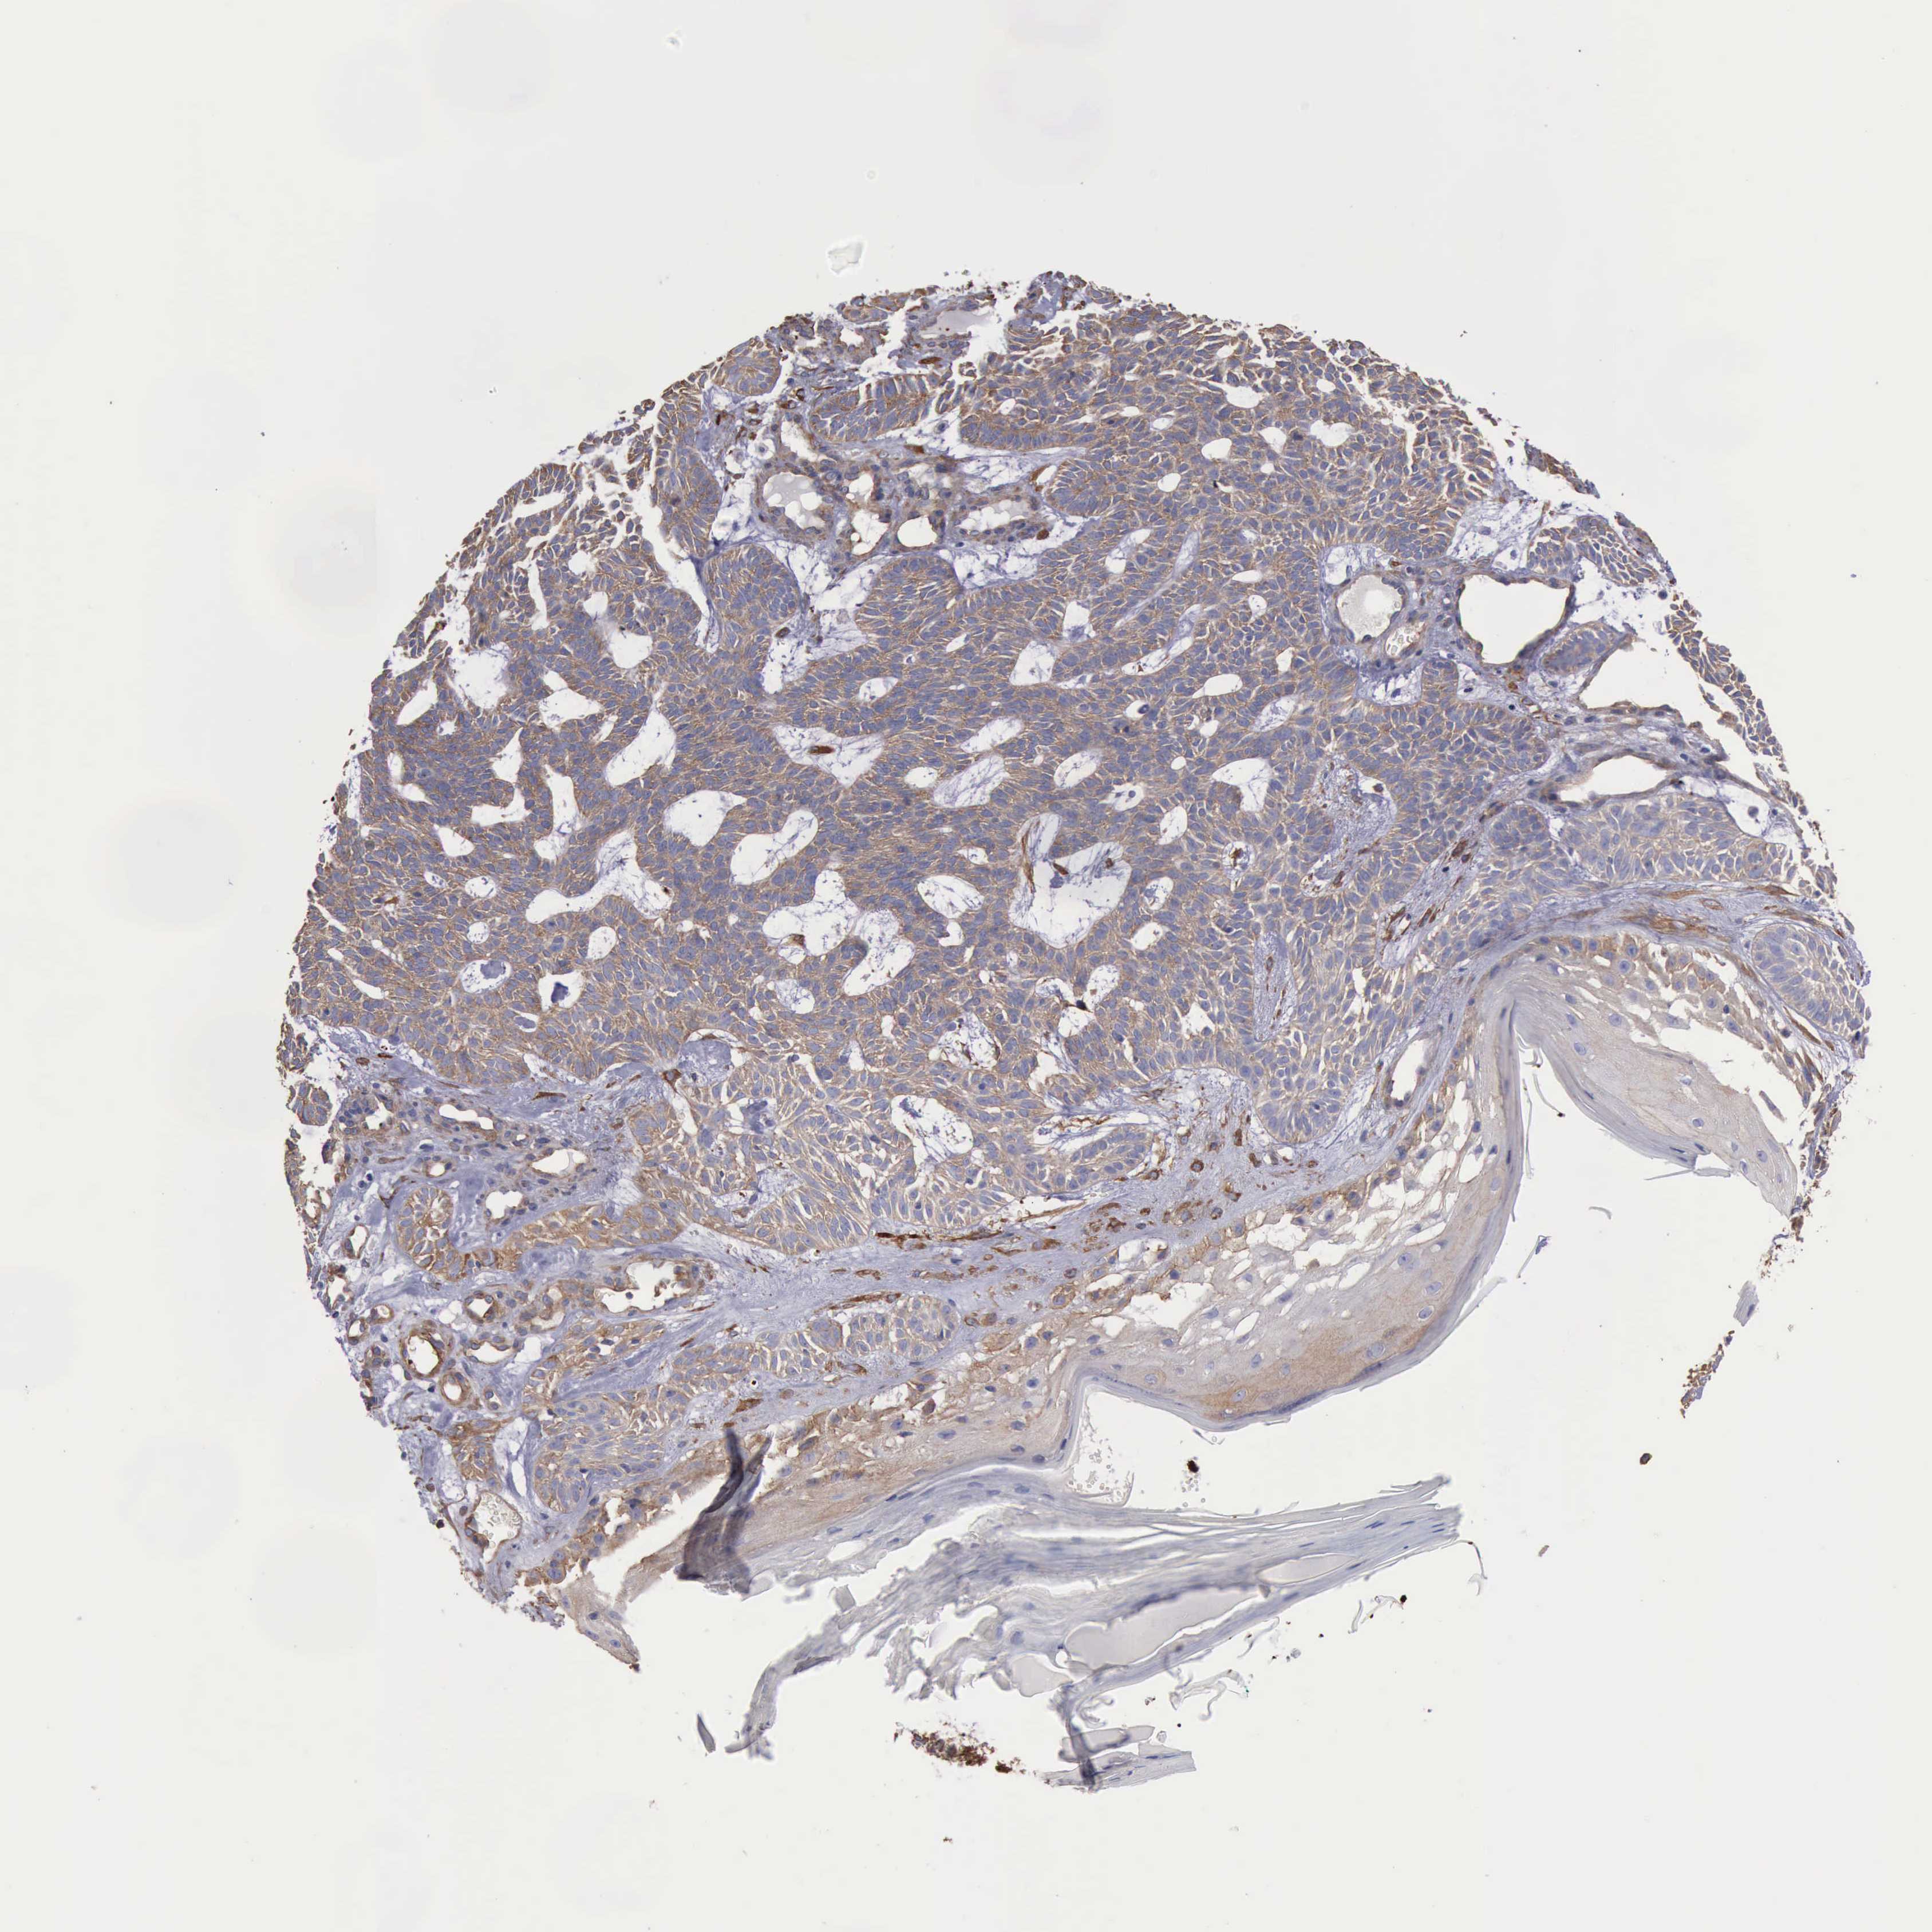

SKIN CANCER - Protein expressioni

A mouse-over function shows sample information and annotation data. Click on an image to view it in a full screen mode. Samples can be filtered based on level of antibody staining by selecting one or several of the following categories: high, medium, low and not detected. The assay and annotation is described here.

Each image is clickable and will lead to virtual microscopy that enables deeper exploration of all samples and also displays staining intensity scores, fraction scores and subcellular localization as well as patient and tissue information for each sample.

Antibody HPA001115

Antibody HPA002925

Antibody CAB000356

Staining

High

Medium

Low

Not detected

Intensity

Strong

Moderate

Weak

Negative

Quantity

>75%

75%-25%

<25%

None

Location

Nuclear

Cytoplasmic/membranous

Cytoplasmic/membranous,nuclear

Squamous cell carcinoma, NOS

Basal cell carcinoma